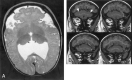

Background and purpose: Analysis of specific features in the brain of patients with holoprosencephaly (HPE) may clarify normal and abnormal brain development and help predict outcomes for specific children. We assessed sulcal and gyral patterns of cerebral cortex in patients with HPE and developed a method of grading brain development.

Methods: Neuroimaging studies (75 MR imaging, 21 CT) of 96 patients with HPE were retrospectively reviewed, with specific attention paid to the cerebral cortex. Thickness of cortex, width of gyri, and depth of sulci were assessed subjectively and by measurement. The angle between lines drawn tangential to the sylvian fissures ("sylvian angle") was measured in each patient with HPE and in 20 control patients.

Results: Thickness of cortex was normal in all 96 patients. Gyral shape and width and sulcal depth were normal in 80 patients. Twelve patients, all with very severe HPE and microcephaly, had reduced sulcal depth, diffusely in eight and limited to the anteromedial cortex in four with lobar HPE. Four patients had subcortical heterotopia, located anterior to the interhemispheric fissure, associated with shallow sulci in the overlying cortex. Sylvian fissures were displaced further anteriorly and medially as HPE became more severe, until, in the most severe cases, no sylvian fissures could be identified. Sylvian angle measurements corresponded closely with severity of HPE, being largest in the most severe and smallest in the least severe cases. All patients with HPE had sylvian angles significantly larger than the mean of 15 degrees measured in the control patients.

Conclusion: The only true malformations of cortical development were subcortical heterotopia. However, diffuse and focal abnormal sulci were observed. We propose our sylvian angle measurement of extent of frontal lobe development as an objective means of quantifying the severity of HPE.